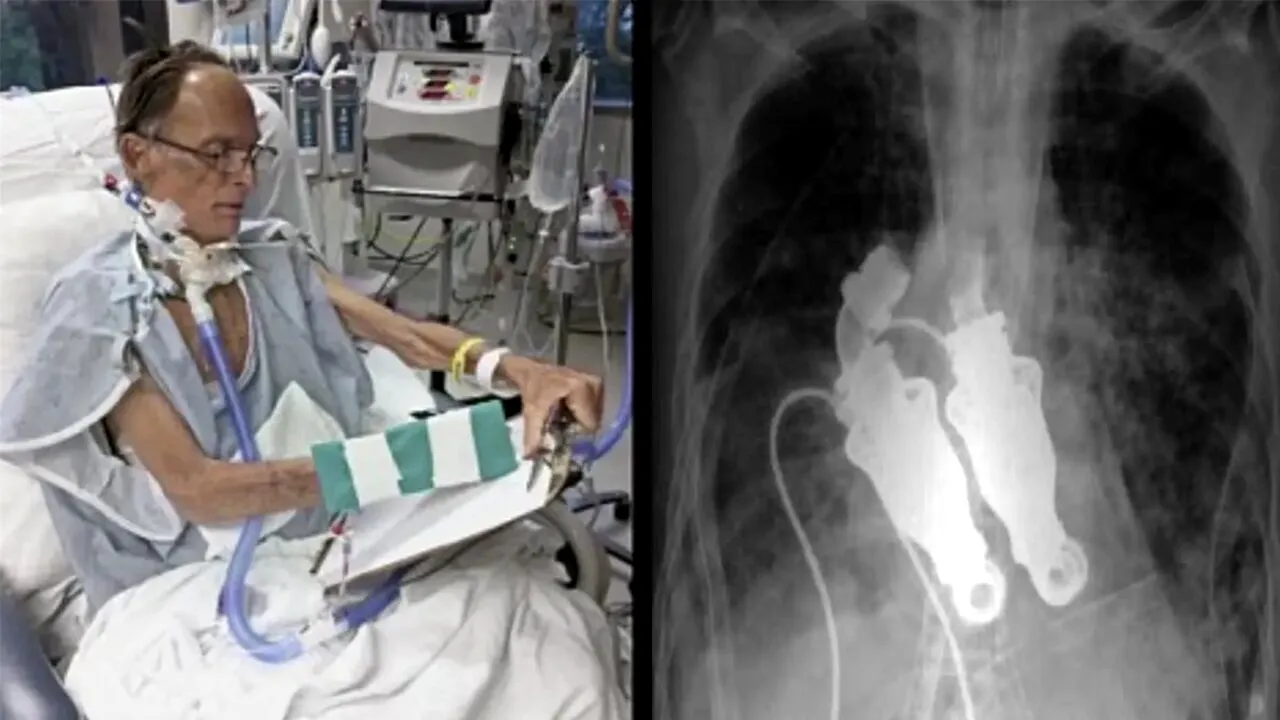

După ce s-au antrenat pe 38 de viței, Cohn și Frazier au trecut la studiile pe oameni – selectând un bărbat de 55 de ani pe nume Craig Lewis, care suferea de amiloidoză, o boală autoimună rară care provoacă acumularea de proteine anormale și, la rândul său, insuficiență cardiacă, renală și hepatică rapidă.

Sursa FOTO: Captură ABC News

În martie 2011, ea i-a abordat pe Cohn și Frazier, care i-au îndepărtat inima soțului ei și au instalat dispozitivul artificial.

„Am ascultat și a fost un zumzet, ceea ce este uimitor. Nu avea puls”, mai spune Linda.

După procedură, Lewis s-a trezit și a început să-și revină.

Cu toate acestea, starea lui a început să se deterioreze atunci când boala i-a atacat ficatul și rinichii și, din păcate, a murit în luna aprilie a acelui an.

Dar a reușit să trăiască mai mult de o lună cu această inimă fără puls, medicii săi spunând că pompele au funcționat impecabil.